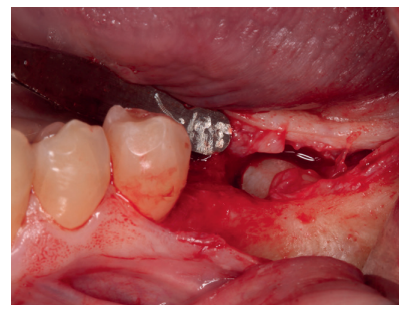

En una primera fase, se llevó a cabo la extracción del 3.7 y se empleó el mismo diente para realizar una preservación del defecto. Se realizó una anestesia troncular del nervio dentario inferior, nervio lingual y nervio bucal del lado izquierdo con articaína al 4% y adrenalina 1: 100,000 (Ultracaine®, Normon SL, Madrid, Spain). Se procedió a realizar una incisión supracrestal sin descargas y un despegamiento mucoperióstico a espesor total, asegurando la protección del colgajo lingual (Figura 3). Se realizó odontosección coronal para facilitar su extracción y, una vez removidas las raíces, se regularizaron los bordes y se dejó preparado para recibir el injerto (Figura 4).